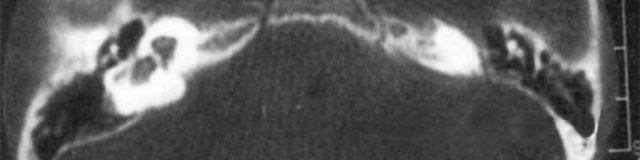

主要依靠顳骨高分辨CT和內(nèi)耳MRI。

雙側(cè)內(nèi)耳畸形:左側(cè)無(wú)內(nèi)耳迷路及內(nèi)耳道機(jī)構(gòu),為米歇爾畸形;右側(cè)空耳蝸及前庭擴(kuò)大,為先天性耳蝸畸形